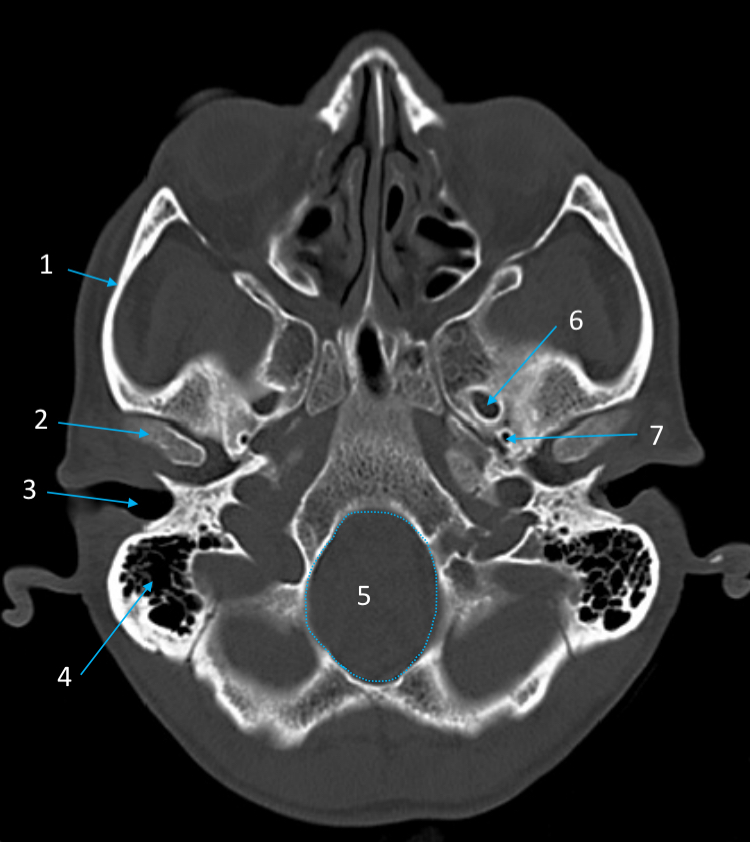

Mandible

ID bone

Maxilla

ID bone

Frontal sinus

ID structure

Pituitary fossa

ID structure

Occipital

ID bone

Lambdoid suture

ID structure

Frontal sinus

ID structure

Orbital margin

Orbit

Maxillary sinus

ID structure

Mandibular condyle

ID structure

Inferior nasal concha

ID structure

Hard palate

ID strucutre

Gonial angle

ID strucutre

Petrous ridge

ID structure

Groove of middle meningeal a.

ID structure

Roof of orbit

ID structure

Frontal sinus

ID structure

Pituitary fossa

ID structure

Petrous ridge

ID structure

Sphenoid sinus

ID structure

Hard palate

ID structure

Mastoid air cells

ID structure

Zygomatic arch

ID structure

Mandibular condyle

ID structure

External auditory meatus

ID structure

Mastoid air cells

ID structure

Foramen magnum

ID structure

Foramen ovale

ID structure

Foramen spinosum

ID structure